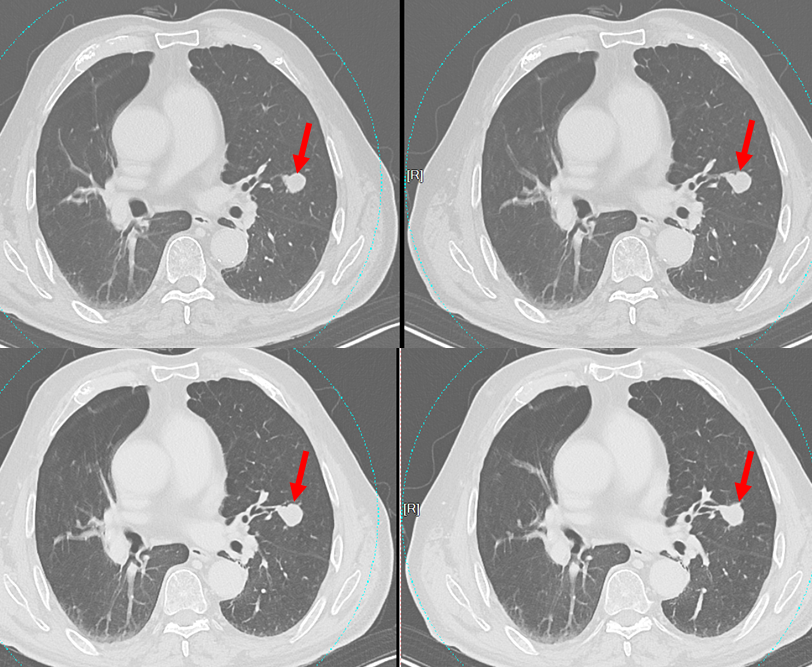

周围型肺小细胞肺癌1例|影像读片

病例1

• 男,80岁

• 主诉:发现肺结节7月余,增大2月

• 现病史:患者7月前发现肺结节,后定期复查,未特殊治疗,2月前发现结节增大伴胸闷气促,无头晕头痛,无胸痛咯血,无发热乏力,无双下肢水肿。现患者为求进一步治疗,至我院门诊就诊,门诊拟“肺结节”收治入院。病程中,患者神清、精神可,睡眠一般,食欲可,二便正常,体重无明显改变

• 个人史:既往吸烟饮酒史,现已戒烟

• 影像学检查:3536585,2025-11-10 胸部CT增强

影像学表现